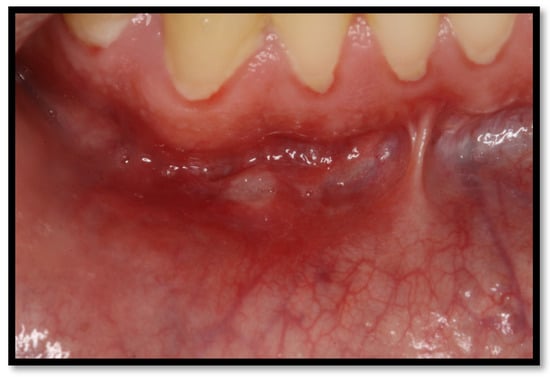

6.1. Minor Aphthous Ulcers

6.2. Major Aphthous Ulcers